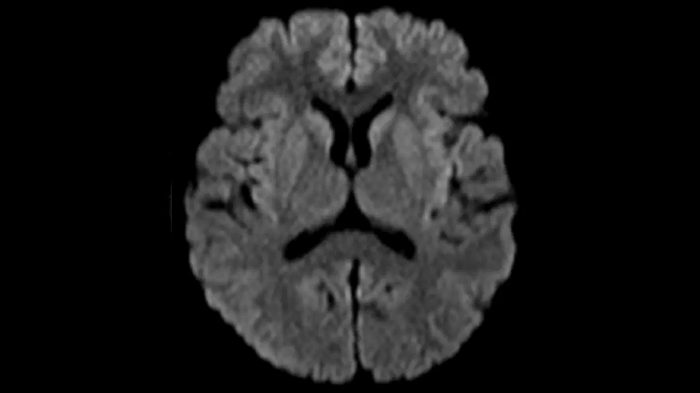

DWI b1000

Exceptional diffusion-weighted imaging with MAGNETOM Free.Star.

PAT 2

0.7 x 0.7 x 5.0 mm2

TA 2:53 minutes

MAC-ID: 7aaaa0195.

MAC-ID: 7aaaa0195. Image Credit: Siemens Healthineers